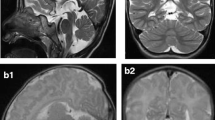

Patient summary

The proband is the first child to nonconsanguineous British Caucasian parents who was delivered at 40 weeks’ gestation after an uncomplicated pregnancy. Birth weight was 2.92 kg (9th percentile) and head circumference 32 cm (0.4th percentile). Physical examination was normal. At 16 h of age, she developed hypotonia and encephalopathy associated with hypoglycaemia, raised anion gap and metabolic acidosis with unrecordably high lactate. In intensive care, she remained unresponsive; acidotic and arterial lactate was 14 mmol/L. Creatine kinase was mildly elevated, and there was mild tubulopathy. Liver function tests were deranged, with abnormal coagulation profile. Workup for a treatable inborn error of metabolism and bacterial or viral pathogens was negative. Initial supportive evidence of mitochondrial dysfunction included high concentrations of proline and alanine in plasma, increased excretion of lactate and pyruvate in urine and reduction in homovanillic acid to 5-hydroxyindoleacetic acid ratio in cerebrospinal fluid (CSF) (Table 2). A muscle biopsy taken at day nine of life showed normal histology. Spectrophotometric assays of RCE activity (as described by Hargreaves et al. 2002) revealed mild reduction of cytochrome oxidase (complex IV) activity relative to citrate synthase (0.011, normal 0.014–0.034). Activities of complex I [nicotinamide adenine dinucleotide (NADH) ubiquinone reductase] and complexes II + III (succinate cytochrome c reductase) were normal (Table 2). Initial magnetic resonance imaging (MRI) of the brain revealed a small pons and dysplastic cerebellum with large bilateral cysts. A small lactate peak was resolved on MR spectroscopy (Fig. 1a, d and g).

A-I: a–c Axial T2-weighted magnetic resonance (MR) images of the brain taken at 5 days, 6 weeks and 7 months of age showing progressive loss of cerebral volume with delayed myelination and relative sparing of the basal ganglia. d–f Coronal T1-weighted MR images of the brain at 5 days, 6 weeks and 7 months of age demonstrating a butterfly pattern of cerebellar hypoplasia with bilateral cysts (+). There is progressive cerebellar volume loss that is most marked between 5 days and 6 weeks but is out of proportion to the degree of supratentorial brain atrophy. g–i Sagittal T1-weighted MR images of the brain at 5 days, 6 weeks and 7 months demonstrating marked progressive cerebral atrophy with progressive thinning of the pons (*), corpus callosum (**) and some degree of optic nerve atrophy (***), particularly between the first two scans

By day 3, the patient was extubated and blood biochemistry had normalised. At 10 days of age, she had a structurally normal eye examination, she was mildly hypotonic but alert, she fed orally and was discharged from hospital. At 4 weeks of age, she re-presented with status epilepticus requiring reintubation. She had frequent jerks, spasticity and fluctuating consciousness level. Her head circumference was 35 cm, now well below the 0.4th percentile for age. There were no biochemical abnormalities detected in blood and urine. Electroencephalogram (EEG) showed severely abnormal background with long periods of marked attenuation, interrupted by sharpened slow activities. Repeat MR imaging of the brain showed remarkable loss of cerebral and cerebellar volume with thinning of the corpus callosum and optic nerves. The basal ganglia remained relatively spared (Fig. 1b, e and h). Over the following 6 months she made no developmental progress, had poor visual attention, no social smiling and continued to have a severe combined seizure and movement disorder. After recovery from prolonged status epilepticus, repeat EEG showed bilateral frontocentral epileptiform discharges, with left-sided predominance. The background showed bilateral anterior more than posterior slowing, suggesting underlying cerebral dysfunction. Repeat brain MR imaging showed minimal worsening (Fig. 1c, f and i). At 12 months, she had near-continuous jerks interrupted by clinically correlated, electrographic seizures, disturbing sleep and required frequent sedation. She was almost entirely dependent on nasogastric feeds, with some pureed food. Auditory and flash visual evoked potentials were absent, with normal flash electroretinograms suggesting profound sensorineural hearing and visual loss. Ophthalmological examination revealed a structurally normal anterior segment, with pupils reacting sluggishly to light, gross pallor of mildly hypoplastic, cupped optic discs with normal intraocular pressure and gross thinning of the nerve fibre layer. This is consistent with secondary optic atrophy associated with loss of function of her anterior vision pathways.

Our case demonstrates the consistent neuroimaging finding of marked flattening or butterfly shape (Namavar et al. 2011b) of the cerebellum and cerebral volume loss, which appears to be progressive—in our patient, rapidly progressive—and is associated with concordant microcephaly. Cerebral and cerebellar atrophy is also observed in PCH3. In addition, these patients have corpus callosum thinning and early-onset optic atrophy (Rajab et al. 2003; Zelnik et al. 1996; Durmaz et al. 2009), which was observed for the first time in PCH6 in our patient (Table 3). Cerebellar cysts seen are a rare neuroradiological finding recently reported in a child with PCH2 due to TSEN54 mutations (Namavar et al. 2011b). The combination has also been described in association with bilateral frontoparietal polymicrogyria due to mutations in GPR56 (Chang et al. 2003; Piao et al. 2005). Cysts are also associated with congenital muscular dystrophies due to defects in dystroglycan glycosylation (Barkovich 1998; Clement et al. 2008). The specific neuroradiological changes seen in PCH6 are of interest, as they allow the potential for rapid recognition and genetic diagnosis, thus bypassing the need for muscle biopsy.